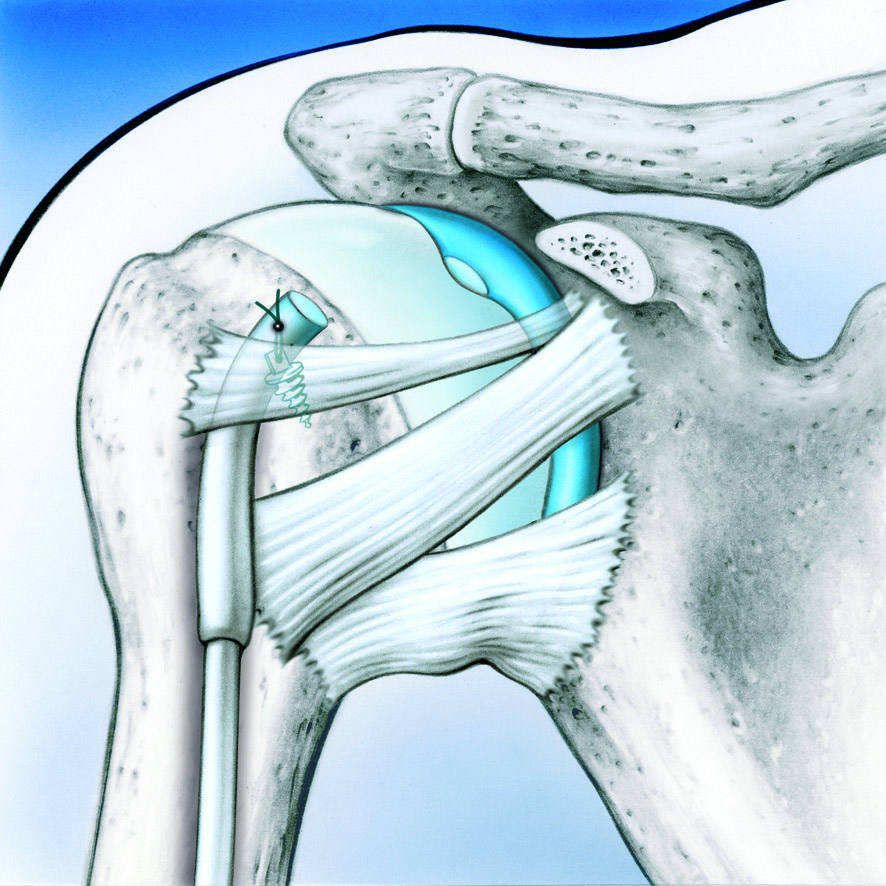

Artroscopia Hombro